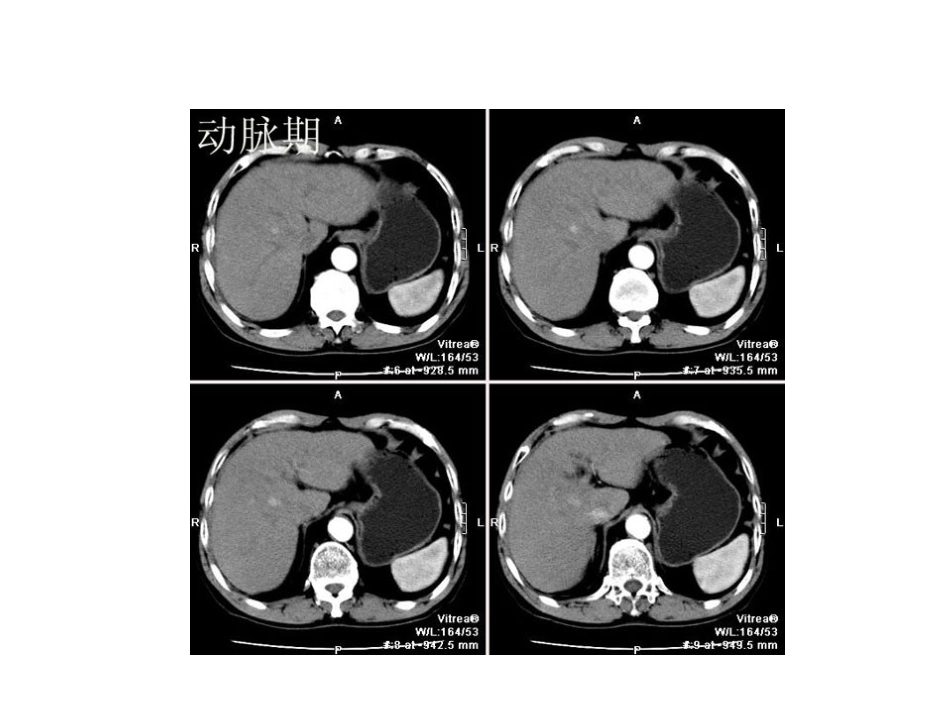

小肝癌的CT表现•小肝癌的定义:•1、单个结节最大直径≤3cm;•2、相邻两个结节,结节直径之和≤3cm。•小肝癌的临床特征:•1、小肝癌发病隐匿,病人无明显自觉症状;•2、大部分病例有慢性乙肝及肝硬化基础;•3、大部分患者AFP升高,少数患者AFP在正常范围。•小肝癌的典型CT表现:•1、平扫呈低密度或等密度;•2、动脉期高密度(高于肝实质,低于同层主动脉);•3、门脉和延迟期为低密度。小肝癌的典型CT表现病例一男性,67,B超肝右叶结节低回声病灶,无任何临床症状。肝右叶小病灶,大小约15mmX18mm,CT平扫几近等密度,动脉期明显完全强化,静脉期回落为等密度,平衡期为低密度,边缘不清晰。小肝癌的典型CT表现病例二是在肝硬化基础上发生的小肝癌,平扫示肝右后叶一低密度结节,动脉期病灶呈均一高密度强化,门脉期病灶与肝呈等密度,延迟期病灶为低密度!小肝癌的典型CT表现病例三发生在右叶的小肝癌,只是门脉期病灶变为低密度了,其它的与上一例表现差不多,也够典型吧!小肝癌的典型CT表现病例四肝左叶的小肝癌,一样的典型!小肝癌的典型CT表现病例五这一例病灶在动脉期强化虽不及上一例明显,但与周周肝脏比较还是明的。小肝癌的典型CT表现病例六这一例病灶动脉期强化比上一例就明显多了,其表现还是典型的肝癌CT表现!小肝癌的典型CT表现病例七是发生在胆囊窝旁的小肝癌!小肝癌的典型CT表现病例八发生在肝右叶的小肝癌。•小肝癌的少见CT表现主要有以下几种:1、动脉期和门脉期肿瘤都呈全瘤范围强化,强化密度都高于肝。2、动脉期肿瘤强化密度高于肝且接近同层主动脉强化密度。门脉期肿瘤密度迅速下降低于肝。3、动脉期肿瘤边缘呈高密度环形强化。4、动、门双期肿瘤强化密度都低于肝。小肝癌的少见CT表现病例一这一例门脉期病灶密度比肝脏要高,不太符合典型的表现。小肝癌的少见CT表现病例二这一例门脉期病灶密度更高,但是延迟扫描病灶还是呈低密度了。小肝癌的少见CT表现病例三动脉期肿瘤强化的过头了,密度高于肝且接近同层主动脉强化密度。门脉期肿瘤密度迅速下降低于肝。小肝癌的少见CT表现病例四动脉期肿瘤边缘呈高密度环形强化。小肝癌的少见CT表现病例五是动、门双期肿瘤强化密度都低于肝的小肝癌小肝癌的少见CT表现病例六也是动、门双期肿瘤强化密度都低于肝的小肝癌,属少见表现小肝癌的少见CT表现病例七也是动、门双期肿瘤强化密度都低于肝的小肝癌,属少见表现。小肝癌的其它少见CT表现病例一1、平扫呈等密度的小肝癌小肝癌的其它少见CT表现病例二2、门脉期呈等密度的小肝癌小肝癌的其它少见CT表现病例三2、门脉期呈等密度的小肝癌之二小肝癌的其它少见CT表现病例四3、动脉及门脉双期均呈等密度的小肝癌小肝癌的其它少见CT表现病例五4、平扫及动脉期均呈等密度的小肝癌小肝癌的其它少见CT表现病例六5、动脉期呈等密度强化的小肝癌小肝癌的其它少见CT表现病例七6、动脉期呈小结节强化的小肝癌小肝癌的其它少见CT表现病例八7、门脉期呈中心性斑点状强化的小肝癌小肝癌的其它少见CT表现病例九8、壁上结节呈双重血供的小肝癌小肝癌的其它少见CT表现病例十9、瘤内明显坏死的小肝癌小肝癌的其它少见CT表现病例十一10、含脂肪的小肝癌;小肝癌的其它少见CT表现病例十二11、门脉期肿瘤边缘呈高密度环形强化的小肝癌小肝癌的其它少见CT表现病例十三12、动、门双期都呈高密度环形强化的小肝癌小肝癌的其它少见CT表现病例十四13、浸润性生长的小肝癌